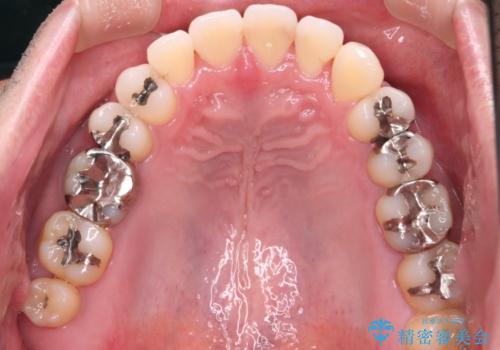

【メタル装置】1本のみ抜歯してワイヤー矯正

- 30代男性

- 矯正装置

- メタル装置

- 右上2番目の歯が舌側転位していることと前歯の叢生(がたつき)を主訴に来院されました。

右上の犬歯が初診時よりかなり歯根露出しており、矯正の力をかけるとさらに歯根露出するリスクがあるため、右上の2番目の歯を前に出すためにも

右上の犬歯を抜歯して歯並びを整える治療計画を立てました。

下のがたつきをとるために、IPR(歯と歯の間を削る処置)も行って歯を並べていきます。